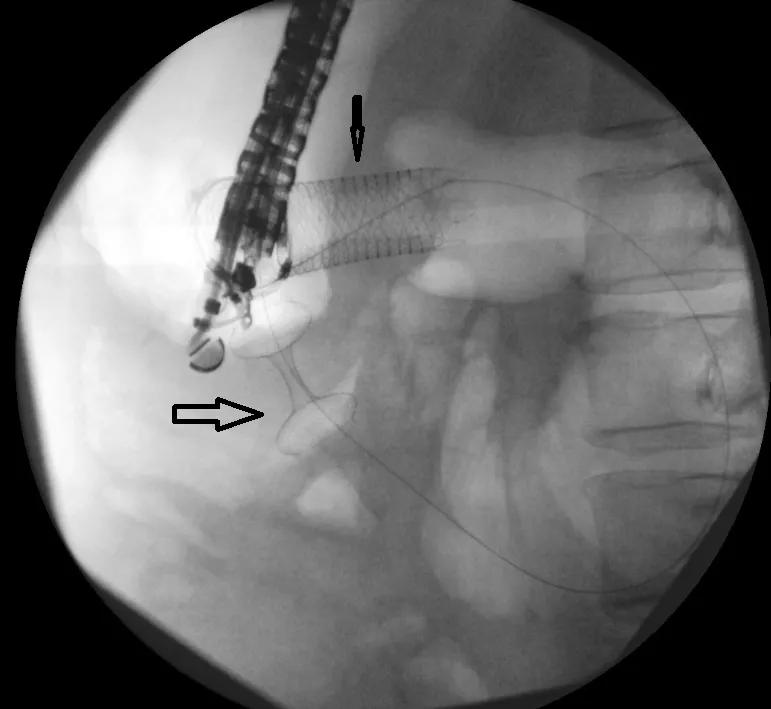

Endoscopic ultrasound-guided gastrojejunostomy (EUS-GJ) is a procedure in which physicians use an endoscope equipped with an ultrasound, camera, and electrocautery-enhanced lumen-apposing, self-expanding metal stent to create an anastomosis between the stomach wall and part of the small bowel loop beyond the area of blockage. This allows food to bypass the blockage and once again pass through the stomach and into the intestines.

To perform the EUS-GJ, Dr. Chahal and colleagues first anesthetized the patient and then inserted the endoscope into the patient’s mouth, passing through the stomach and into the small bowel. The camera on the instrument helped her assess the location and length of the blockage and helped her locate a section of the small bowel loop that was closest to the stomach but beyond the blockage. Finally, using ultrasound guidance, she used the cautery to puncture an opening in the stomach and small bowel loop and deployed a 2-cm long stent with flared ends (dumbbell shaped), which joined together the stomach and small bowel loop, creating an anastomosis.